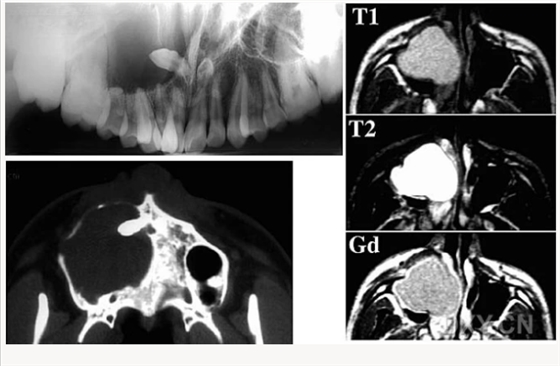

成釉細(xì)胞瘤

鼻鄂囊腫

腺淋巴瘤[沃辛瘤